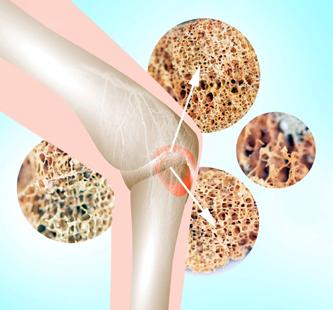

Osteoporoza și legătura acesteia cu afecțiunile tiroidiene Dr. Negoita Casandra

Identificarea polimorfismului rs35705950 al genei MUC5B și importanța diagnostică

Osteodensitometru

• Precizie superioară, comparabilă cu aparate DEXA

• Senzori care se auto poziționează

• Locul de măsurare: osul calcaneu

• Timp de măsurare rapid (15 secunde)

• Măsuratori: BQI, BUA, SOS, T-score, Z-score

• Indici estimați in Vivo: SOS (C.V.%) 0,2; BUA (C.V. %) 1,5; BQI (C.V. %) 1,5

• Frecvența central a sondei: 0,5 MHz

• Capacitate de stocare: 10.000 de pacienți

• Metoda de cuplare uscată, pe bază de gel

• Monitor sensibil la atingere (touch screen)

• Imprimantă termică încorporată

• Nu constituie pericol de iradiere